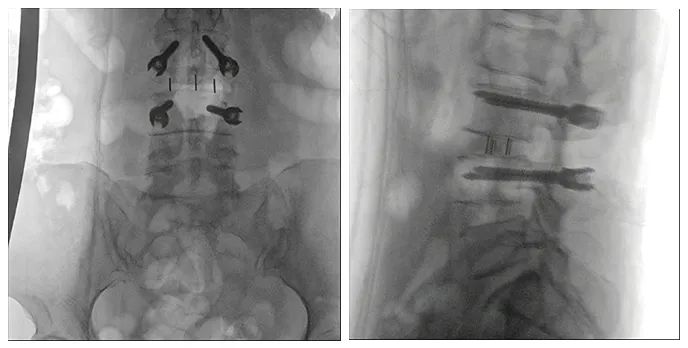

使用普愛醫(yī)療術(shù)中三維導(dǎo)航C臂進(jìn)行透視,根據(jù)透視影像引導(dǎo)確認(rèn)責(zé)任間盤、規(guī)劃手術(shù)方案,充分暴露骨組織,并通過專業(yè)器械切除椎板,暴露神經(jīng)及椎管;在C形臂的引導(dǎo)下,確定責(zé)任間盤上下椎體椎弓根位置,制定進(jìn)針點及進(jìn)針方向,沿椎弓根方向植入脊柱螺釘進(jìn)行固定;放入椎間融合器,加固螺釘。最后再進(jìn)行C形臂透視,確認(rèn)手術(shù)的完成效果。

手術(shù)效果確認(rèn)